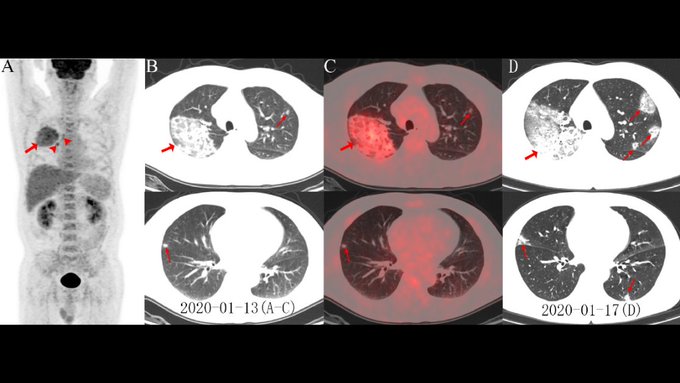

Kuzey Amerika Radyoloji Derneği (RSNA) 44 yaşında corona virüsten ölen bir erkek vakanın akciğer röntgen fotoğraflarını yayınladı.

Röntgen filmlerinde akciğerlerin çevresindeki sıvının nasıl zamanla daha belirgin ve yoğun bir hale geldiğini gözler önüne seriyor.

Visit the @radiology_rsna COVID-19 Special Focus page for newly published images of COVID-19 using FDG PET/CT and images assessing the inflammation burden with volume-rendered chest CT. https://pubs.rsna.org/2019-ncov #CoronavirusOutbreak #CTRad

Çin vatandaşı hastanın yaklaşık iki hafta boyunca ateş ve öksürükten şikayetlerinin ardından sonra 25 Aralık 2019'da hastaneye kaldırıldığı verilen bilgiler arasında. Doktorlar hastada ilk olarak zatürre ve akut solunum sıkıntısı sendromu teşhisinde bulundu.

Hasta tedavi edilmesine rağmen 1 hafta sonra corona virüse bağlı semptomlar nedeniyle yaşamını yitirdi. Corona virüs hastalarının çoğunda ters bir çember işareti belirgin bir şekilde göze çarpıyor. Akciğerlerin alt köşelerindeki beyaz lekeler virüs ün varlığını gözler önüne seriyor.